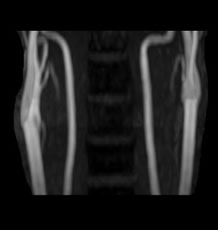

頸動脈エコー

首の血管の内部の様子を超音波で観察します。動脈硬化の様子がよくわかり、血栓ができやすい状態かどうかもわかります。

エコー(超音波診断装置)

HITACHI ARIETTA 60